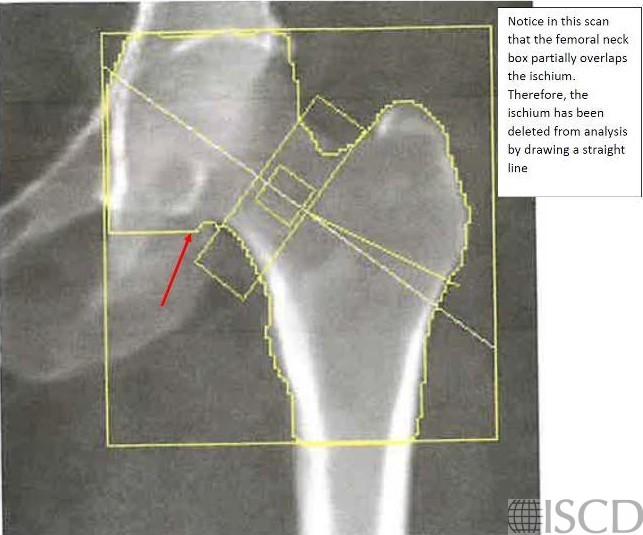

If the femoral neck overlaps the ischium, the ischium can be painted out.

The hip that is scanned is internally rotated using a hip positioner. The hip is internally rotated because that makes the femoral neck parallel to the scanner bed. The default width of the femoral neck box is 15 pixels. The analysis is stepped through and a line is placed on various landmarks (i.e. head of the femur, greater trochanter and bottom of the lesser trochanter) and this positions the global region of interest box of the hip scan. It is the bottom of the hip global region of interest that is most important related to total hip results on a Hologic scan. The bottom of the global region of interest should be 10 pixels below the bottom of the lesser trochanter. The lesser trochanter may be better defined by altering the contrast on the scan. If the femoral neck overlaps the ischium, the edge detection may be altered to paint out that portion of the ischium.